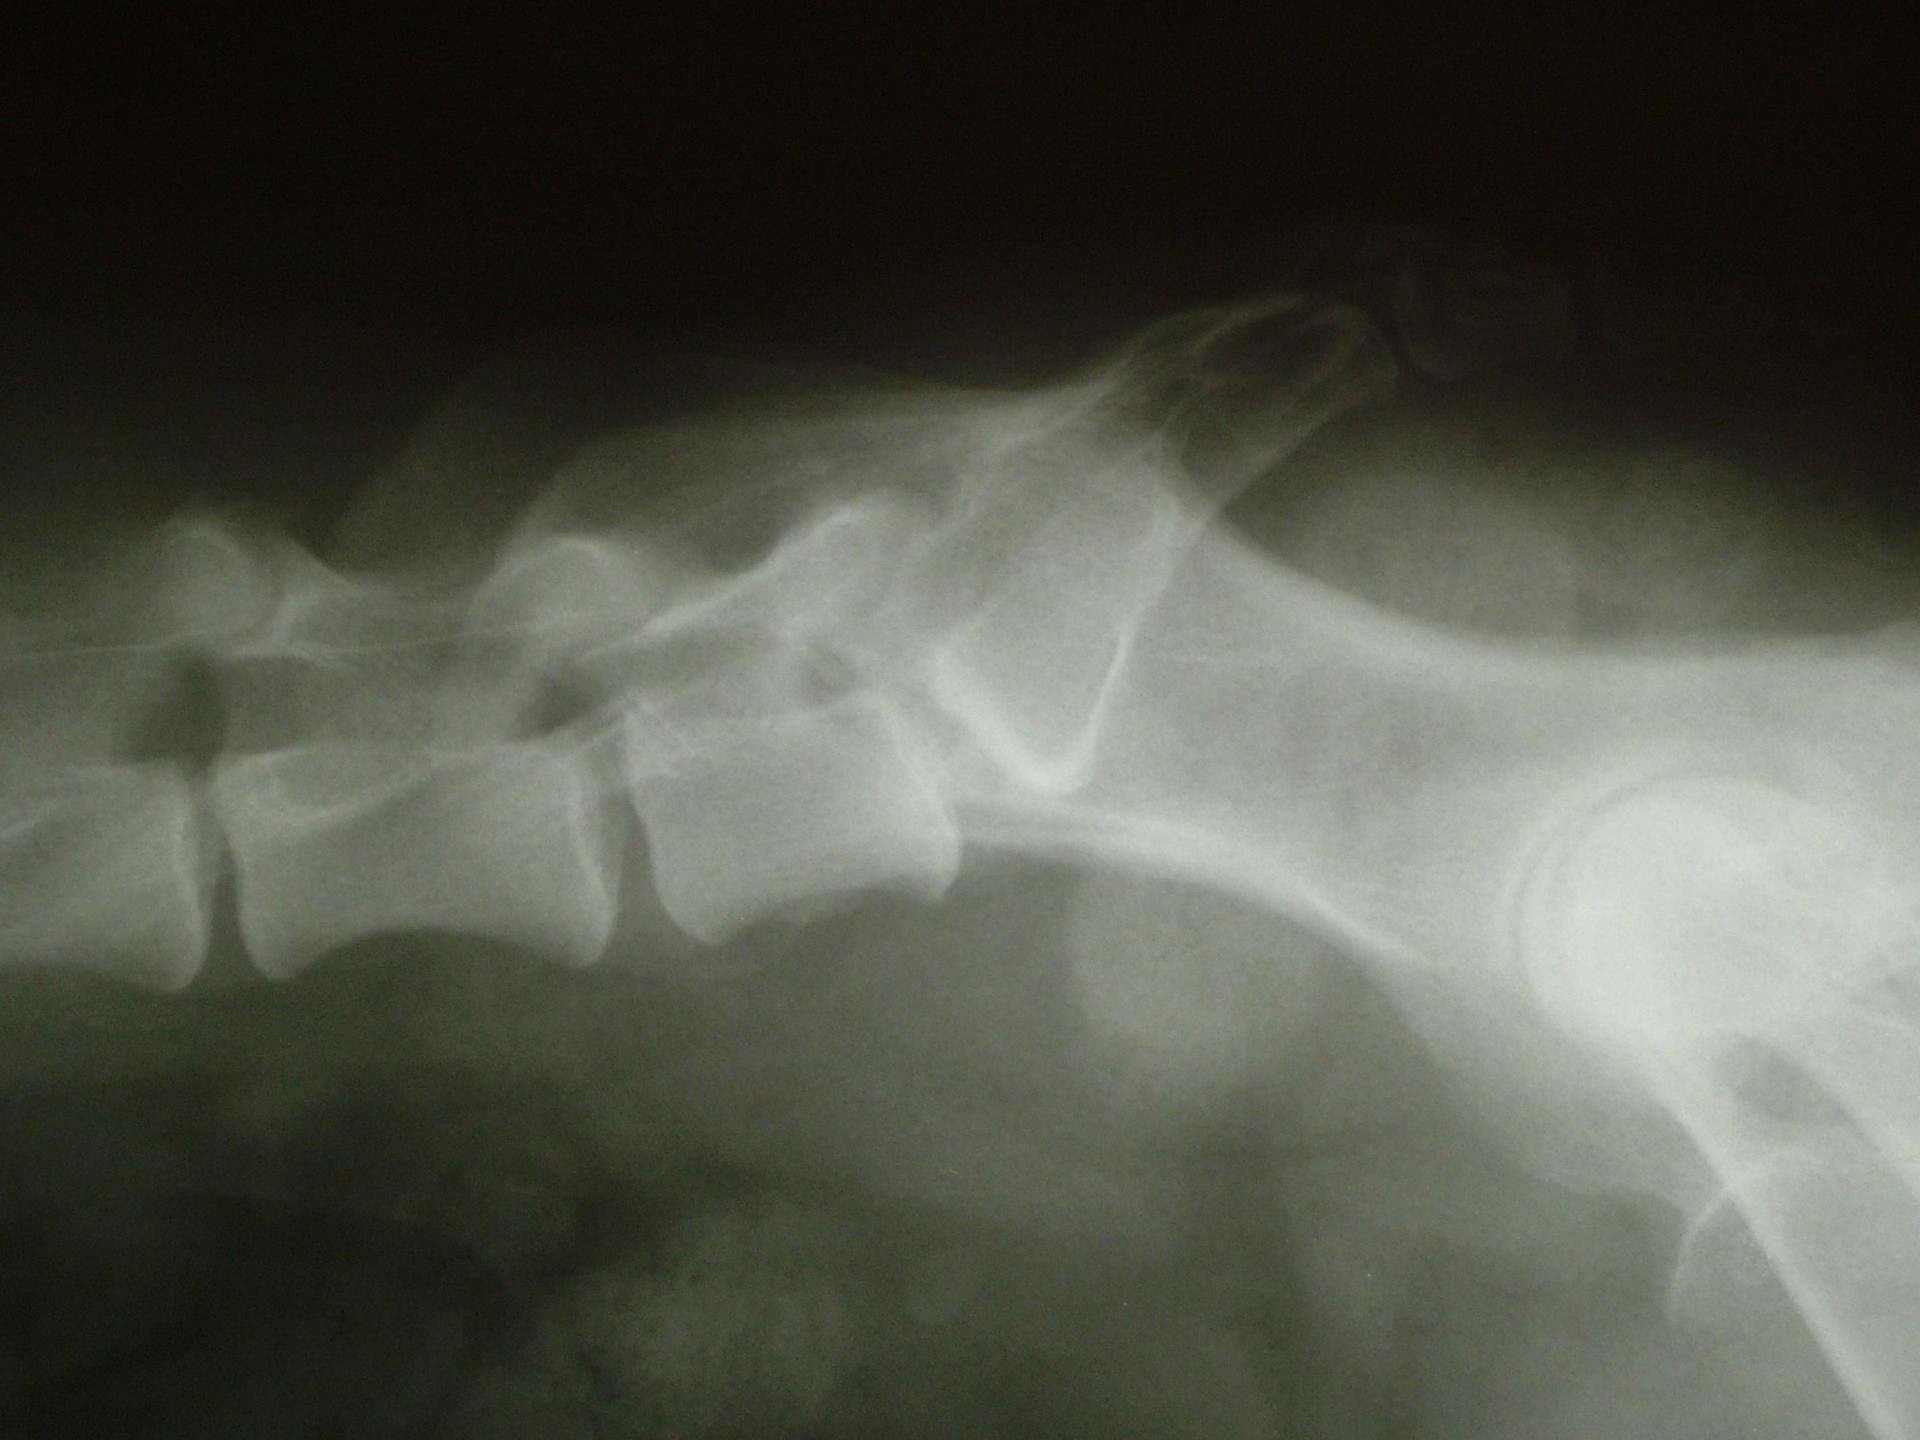

A C.E.C diagnosztikájának legfontosabb lépése a kórelőzmény megismerése után (hátulsó testfél gyengeség, rogyadozás, széklet-vizeletürítési problémák, fájdalom stb.) az alapos klinikai vizsgálat, mely során a gerinctájék fájdalmasságát, a hátulsó végtag reflexeit, a fájdalomérzet meglétét vizsgáljuk.Amennyiben a klinikai tünetek indokolják kiegészítő vizsgálatként elsősorban a röntgenvizsgálat jön szóba, mely során a gerincoszlop ezen szakaszáról oldalirányú felvételt készítünk.

Amennyiben a klinikai tünetek és az oldalirányú röntgenfelvétel alapján a C.E.C. alapos gyanúja felmerül további vizsgálatokkal kell kizárnunk egyéb gerincbetegségeket ill. megerősíteni a C.E.C. diagnózisát.

Az egyik ilyen vizsgálat a gerincfestés vagy myelographia, mely során a gerincvelőt körbevevő térbe (subduralis tér), az agy-gerincvelői folyadékba (liquor) röntgenkontraszt anyagot juttatunk és sorozatos felvételekkel ellenőrizzük annak áramlását. Ennek előnye, hogy a kontrasztanyag lefutása során az egyéb gerincszakaszok is kirajzolódnak, és ezek esetleges betegségeit is diagnosztizálhatjuk. A gerincoszlop hátsó szakaszáról 1db teljesen hajlított és 1 db teljesen nyújtott beállítású RTG felvételt készítünk. Ha a két felvétel között jelentős különbséget tapasztalunk a C.E.C. biztosan diagnosztizálható.A másik invazív diagnosztikai eljárás a durographia, mely során a röntgenkontraszt anyagot a durazsák körüli térbe (epiduralis tér) juttatjuk és így indirekt módon ábrázoljuk a gerincvelő esetleges összenyomatását. A vizsgálat során a kontrasztanyag telődési hiánya jelzi az összenyomatást és annak mértékét.A diagnosztika legmodernebb vizsgálati módszere az MRI vizsgálat, mely során altatásban, invazív beavatkozás nélkül kaphatunk átfogó képet a vizsgálni kívánt gerincszakaszról. Magyarországon állatorvosi diagnosztikai célra csak a Kaposvári Egyetem Diagnosztikai és Onkoradiológiai Intézetében működő berendezés használható.